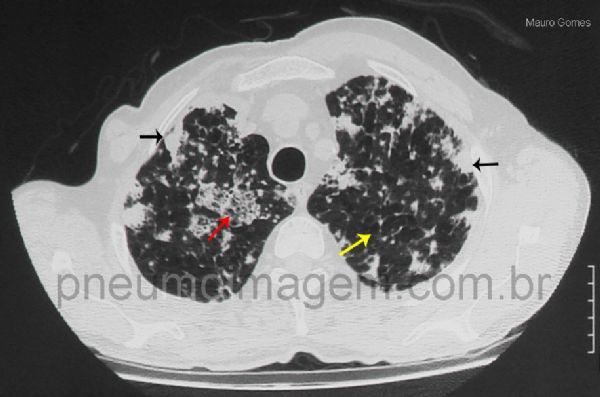

Áreas de opacidades em vidro fosco com septos interlobulares espessados no seu interior (aspecto de pavimentação em mosaico) - seta vermelha. Nódulos confluentes formando áreas de consolidação (seta preta). Áreas com formações císticas compatíveis com enfisema ou pseudobolhas (seta amarela). Estudos atuais de correlação radiológica-patológica postulam que ocorram metástases com disseminação por via aérea (metástases aerógenas) no adenocarcinoma de pulmão. As células cancerosas crescem ao longo dos septos alveolares no local primário destacadas da membrana basal, distribuem-se através das vias aéreas e voltam a fixar e a crescer ao longo dos septos alveolares, longe do foco primário.

Ground-glass opacities with thickened interlobular septa (mosaic pattern) - red arrow. Confluent nodules to form areas of consolidation (black arrow). Areas with cystic formations consistent with emphysema or pseudo-bubbles (yellow arrow). Current studies of radiological-pathological correlation postulate that occur metastases with airborne spread (aerogenous metastases) in lung adenocarcinoma. Cancer cells grow along the alveolar septa at the primary site detached from the basal membrane, are distributed through the airways and return to fix and grow along the alveolar septa, away from the primary focus.